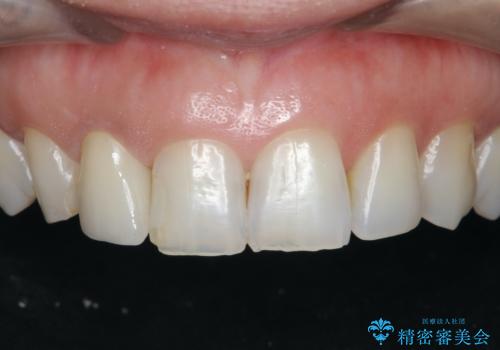

セラミック治療を行う前にきっちりと根管治療を行うことが長期的に持つ可能性を高めます。